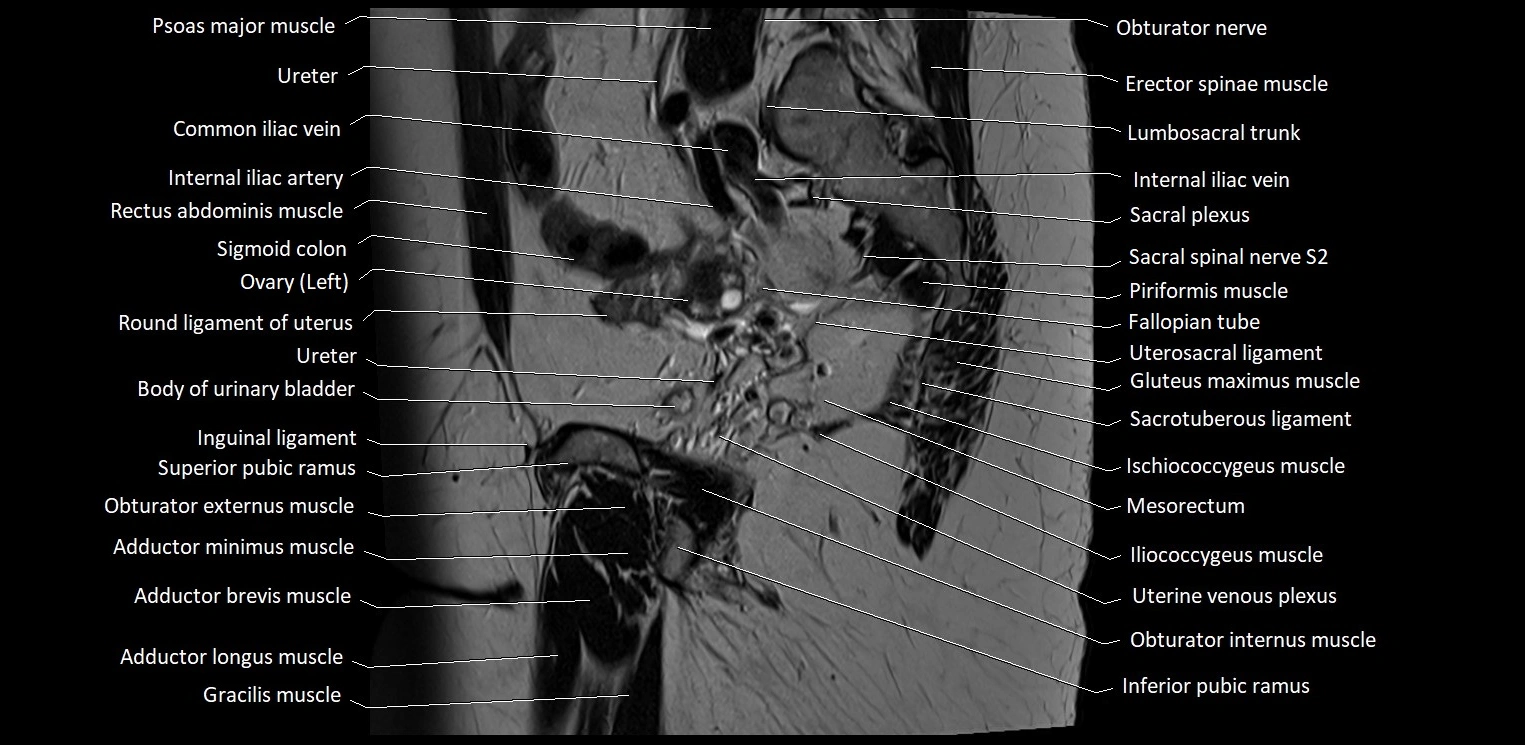

- Adductor brevis muscle

- Adductor longus muscle

- Adductor minimus muscle

- Common iliac vein

- Fallopian tube

- Gracilis muscle

- Iliococcygeus muscle

- Inferior pubic ramus

- Inguinal ligament

- Internal iliac artery

- Internal iliac vein

- Internal pudendal vein

- Left ovary

- Lumbosacral trunk

- Obturator externus muscle

- Obturator internus muscle

- Obturator nerve

- Piriformis muscle

- Psoas major muscle

- Pubic bone

- Sacral plexus

- Sacrospinous ligament

- Sacrotuberous ligament

- Sigmoid colon

- Spinal nerve S2

- Superior pubic ramus

- Superior rectal artery

- Uterine venous plexus

- Uterosacral ligament